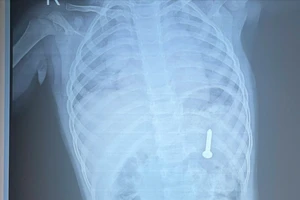

Trước đó, bệnh nhân Trang từng làm việc tại TP Vũ Hán (Trung Quốc) trở về quê ăn tết Nguyên đán có biểu hiện sốt, đau ngực và ho, phải nhập viện vào ngày 24-1. Sau quá trình điều trị bệnh nhân đã hết sốt, không ho và chưa có biểu hiện suy hô hấp.

Bệnh nhân Nguyễn Thị Trang (25 tuổi) đang được điều trị tích cực, đúng phác đồ chuẩn nếu xét nghiệm lại âm tính với virus Corona là có thể xuất viện được.